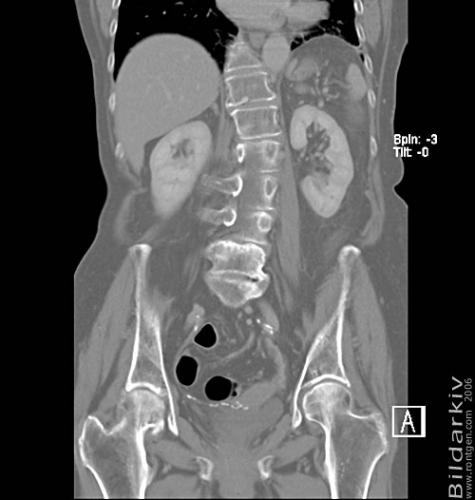

CT colon 34

Datortomografi av tjocktarmen (colon) med infunderad luft i tarmen samt med kontrast i blodbanan. Koronar bildserie.

CT multislice 16